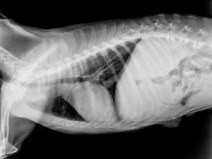

• Soirée Les pièges de la radiographie thoracique

Quel dommage de ne pas exploiter complètement tout ce que l'on peut voir sur des clichés thoraciques. À partir de cas concrets, nous allons explorer toutes les facettes de ces clichés et les pièges à éviter.